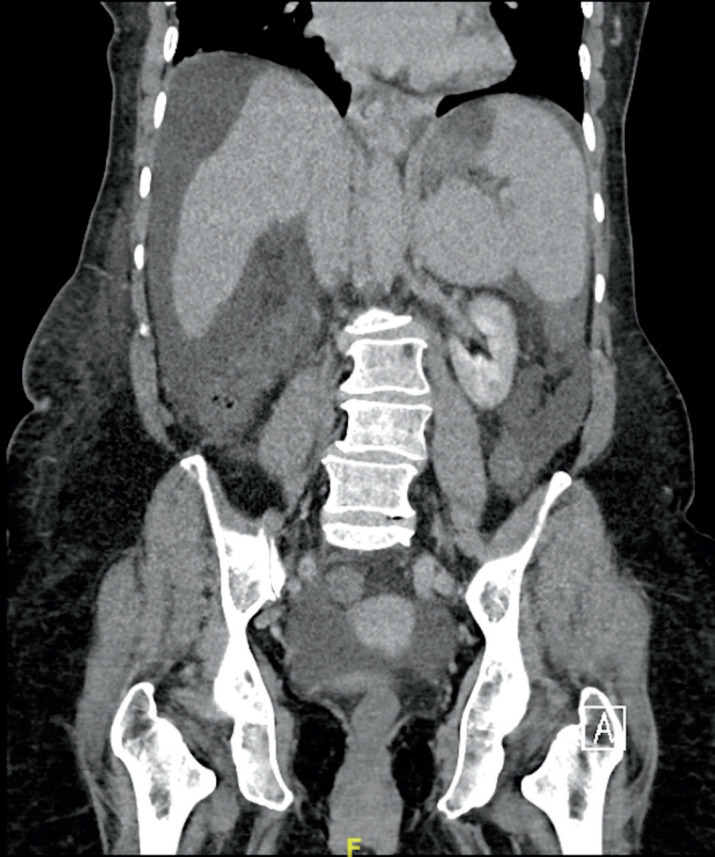

Case presentation: A 65-year-old lady, presented to our emergency department complaining of a left lower quadrant (LLQ) abdominal pain associated with a painful swelling for 9 hours duration. Upon assessment, the patient was jaundiced and haemodynamically stable. Abdominal examination revealed a soft and lax but distended abdomen, with irreducible tender swelling over the LLQ, measuring around 3x2 cm. Laboratory investigations showed anemia, hypoalbuminemia, hyperbilirubinemia, lactic acidosis and prolonged coagulation profile. A contrast-enhanced computed tomography (CT) scan of the abdomen showed evidence of incarcerated left spigelian hernia. Moreover, advanced cirrhosis of the liver was detected with hypertrophy of the caudate lobe, extensive ascites and splenomegaly. After establishing the diagnosis of incarcerated spigelian hernia, with a picture of advanced liver cirrhosis, Child-Pugh-Turcotte (CPT) score of C and a Model for End-Stage Liver Disease (MELD) score of 19 and Mayo score for post-operative mortality of 16% in 7 days and 53% in 30 days. Given the patient's condition which necessitates urgent operative intervention beside the risk of decompensation of pre-existing liver disease and high mortality. Decision was made to proceed with laparoscopic hernia repair. Intraoperatively, ischemic small bowel segment was resected with creation of end ileostomy. Conventional anatomical repair of the hernia defect was performed. Postoperatively, the patient was managed and resuscitated in critical care unit and then discharged home in a satisfactory condition on post-operative day 15. She passed away prior to liver transplantation, thirty-two days post-operatively in a different institution.